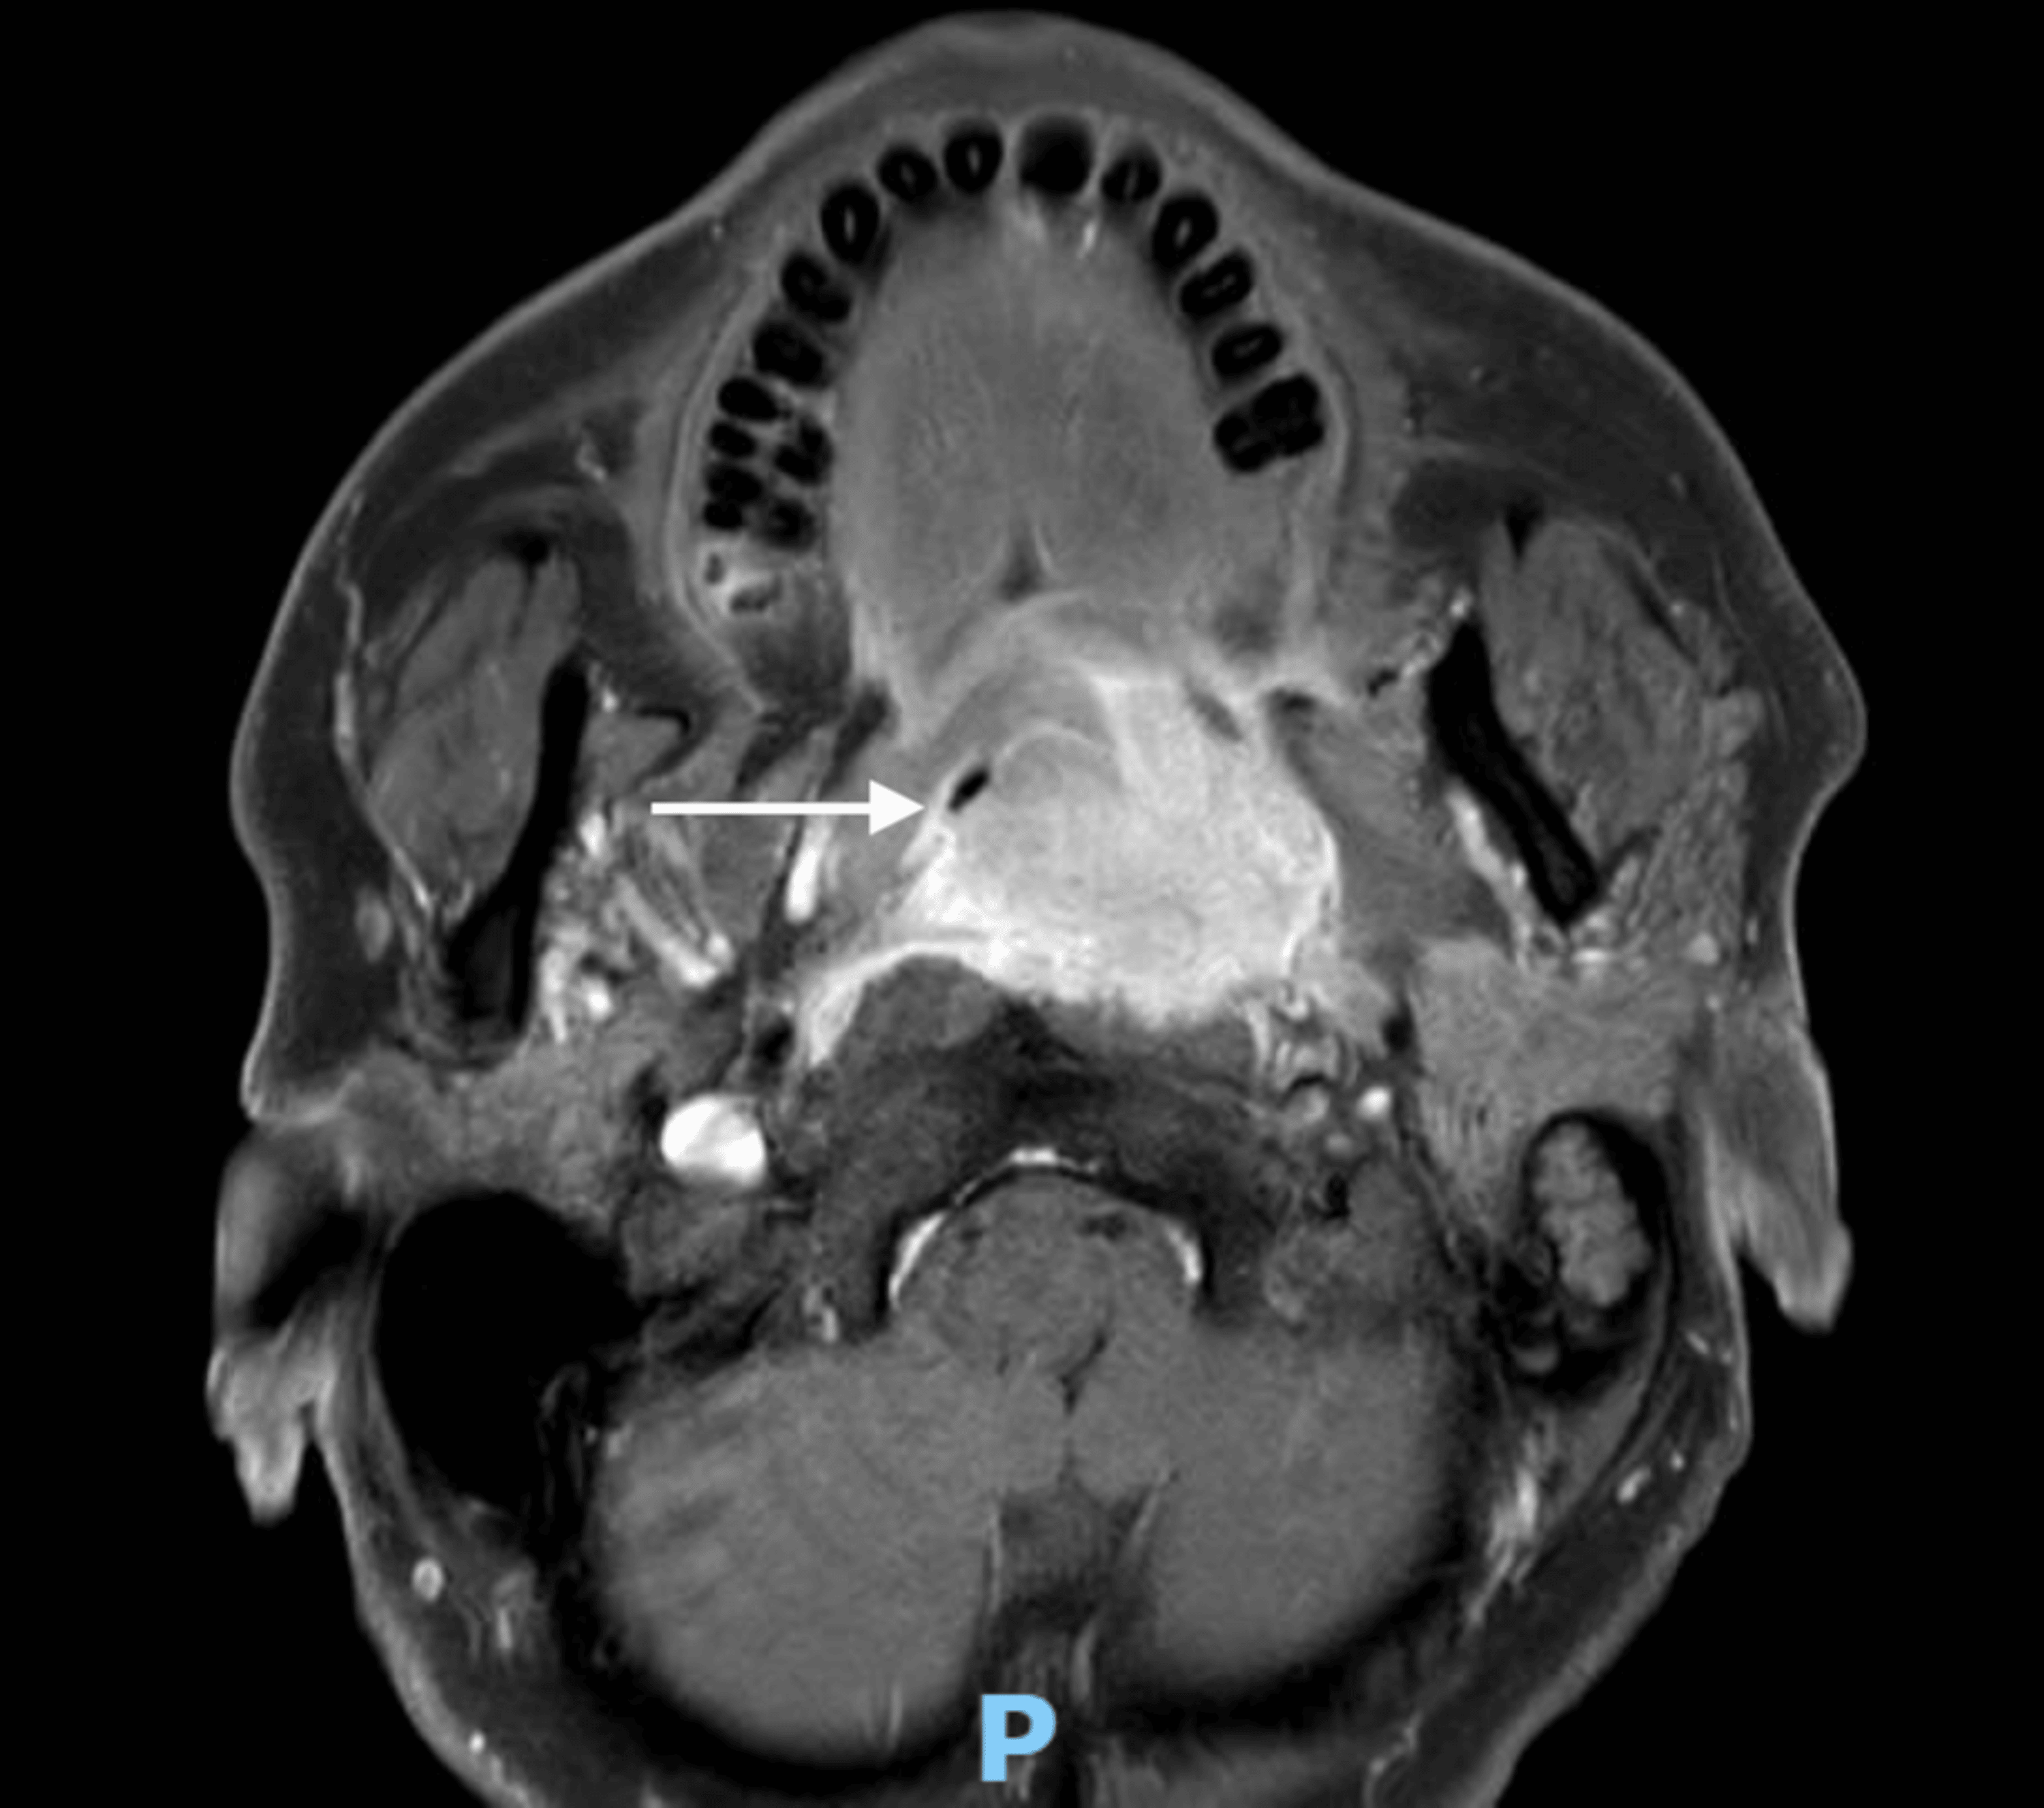

A 61-year-old man with a left tonsillar tumor extending up to the post-nasal space was electively admitted for biopsy, rigid esophagoscopy, and examination under anesthesia. Preoperative MRI of the neck showed a heterogeneous, enhancing, lobulated mass with lobulated margins, approximately 4.7 cm × 4.2 cm × 3.0 cm, centered at the left tonsillar fossa with local extension to the tongue base, soft palate, nasopharynx, retropharyngeal/prevertebral, and parapharyngeal spaces. It crossed the midline, resulting in near-complete effacement of the naso/oropharynx (Figure 10). He had a Mallampati score of 4.